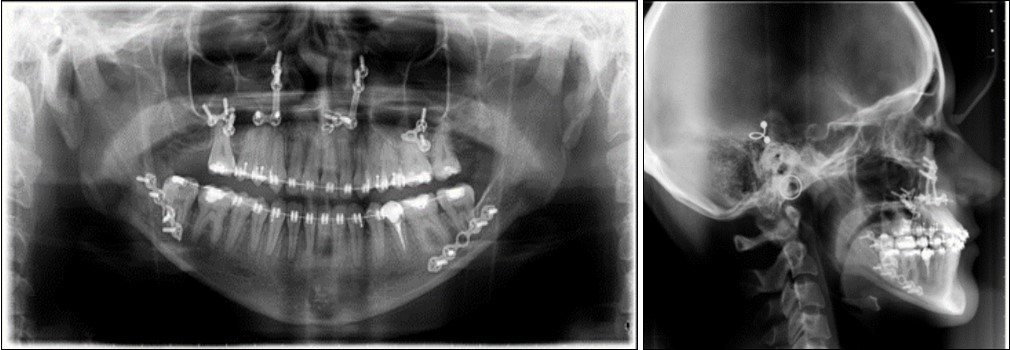

The surgical treatment included Le Fort I osteotomy for impactation and anterior traction of the maxilla. The Obwegeser-Dal Pont method for the set back of the mandible was used. The surgical and post-surgical phase had no complications.

Post-surgical orthodontic treatment was started 4 weeks after the surgery. Wearing of bilateral box elastics was recommended in order to improve interdigitation. (Figure 6) The orthodontic treatment was finished on 0.019x0.025 SS archwires. Post-surgery cephalometric analysis revealed an increase in SNA value by 4 degrees (SNA 82 degrees) and a decrease in SNB value also by 4 degrees (SNB 79 degrees). The patient was now in a skeletal class I, with ANB 3 degrees. An examination of the soft tissue on the radiograph reveales a better relation between the upper and lower lip. (Figure 7).

Figure 7.Post-surgical panoramic and lateral cephalometric radiograph.

The use of digital patient records such as x-rays and digital photos, is particularly useful in cases where patients are treated in interdisciplinary teams.19 In the present case report, collaboration between orthodontic and surgical treatment was a success, with excellent esthetic and functional results. From a skeletal class III (ANB –5 degrees), the increase in ANB angle value was 8 degrees after the bimaxillary surgery, final ANB angle value being 3 degrees and a class I skeletal class.